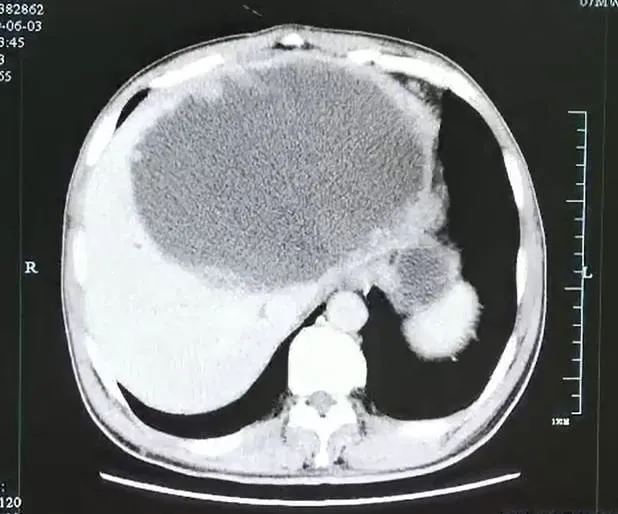

L'abcès après le drainage

2/4

Service de presse

Après drainage, la cavité de l'abcès a rétréci. Toutefois la paroi reste épaisse. Finalement, il a été nécessaire de retirer une partie de l'organe du patient.